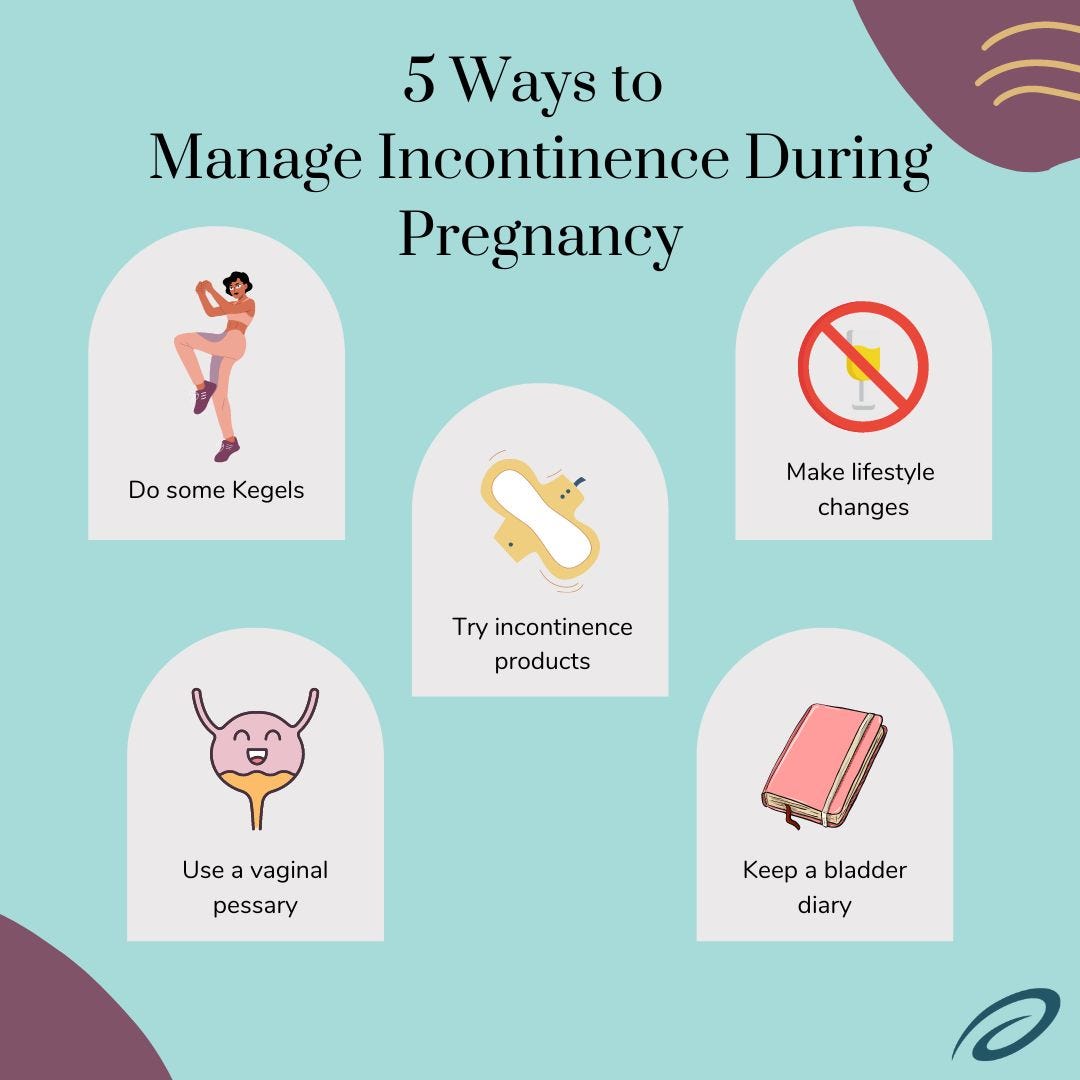

Incontinence During Pregnancy Aeroflow Urology